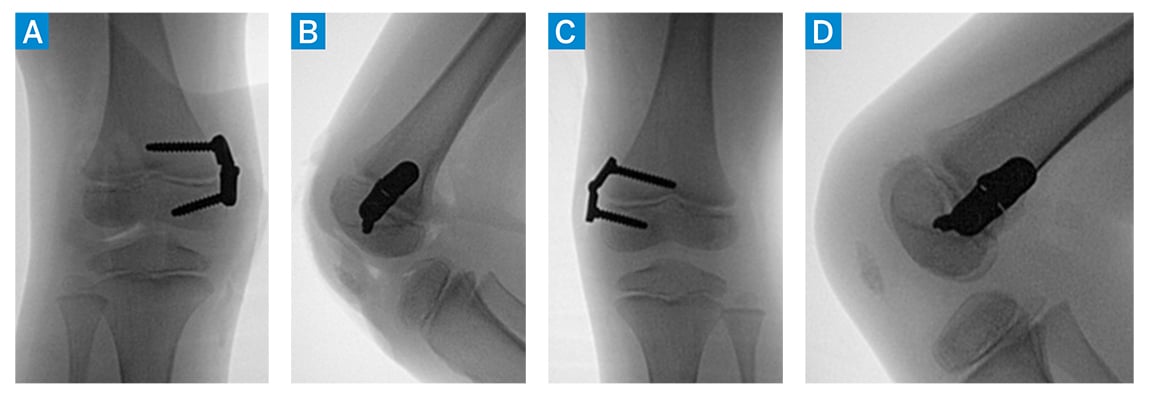

- Bilateral hemiepiphysiodesis to improve valgus alignment (Fig. 2)

Figure 2: (a, b) Anteroposterior (AP) and lateral intraoperative C-arm images of the right knee after hinge knee plate application. (c, d) AP and lateral intraoperative C-arm images of left knee after hinge knee plate application.

In surgery, a pathologic attachment of the iliotibial band to the patella was noted and released. The patient underwent removal of bilateral hinge knee plates 10 months postoperatively (Fig. 3), at which time he was doing well and reported no pain.